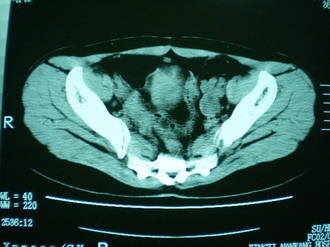

子宫增大,内可见类三角形低密度区,子宫后方可见类圆形团块状影,内部密度不均匀,可见靶样结构,结合病史考虑1子宫后方宫外孕(宫内假孕囊形成)2子宫肌瘤合并妊娠

子宫明显前倾,增大,宫颈增大呈分叶状。子宫直肠窝见不规则形水样低密度。(膀胱胀尿不理想)

考虑:1、宫颈部占位;

2、子宫直肠窝少量积液(盆腔炎所致)。

考虑:1、宫颈部占位(宫颈癌?);

2、子宫直肠窝少量积液。

1、前曲子宫,2、宫颈部占位?3、盆腔及右输卵管积液?宫内积血?4、左侧卵巢囊肿。